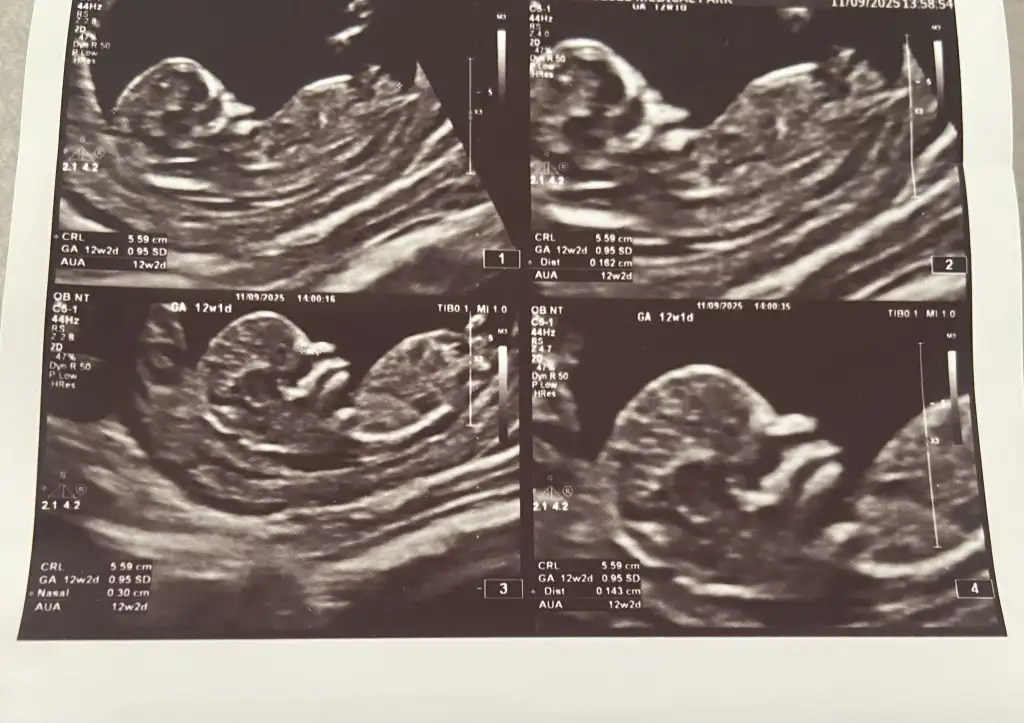

13 haftalık ultrason fotoğrafına göre cinsiyet tahmini?

Bu arkadaşımın 13+3 net değil demişler sizce erkek mi kız mı

Bakın işte burada 3 çizgi🥰 Ama henüz yeni yeni oluştuğu için yanılma payı olabiliyor tabiki😊 Gönlünüzdeki nasip olur inşallah, sağlıcakla